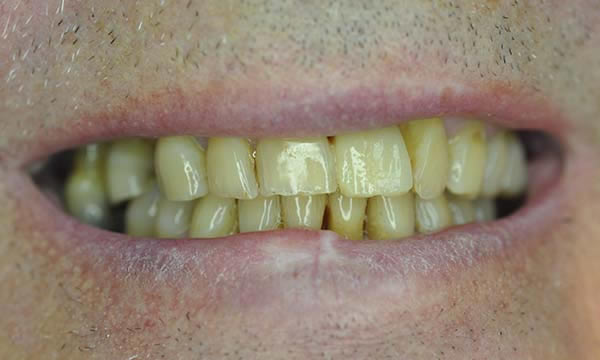

Case E

This lovely lady was referred to Dental Implants .London and treated in her own practice with the help of the referring dentist. The patient came to see us after having an accident as a child which left her upper front four teeth heavily restored. After numerous root canal treatments, apicectomies and crowns, all of the upper anterior incisors started to exhibit signs of external root resorbtion. Over the years the upper central incisors lost over 50% of the root support, over erupted and became loose.

It was very important, given the patients work in a school that she had an adequate temporaries during her treatment and that she was never left without teeth. This was taken care of using a temporary denture.

The delayed immediate protocol was implemented, following extraction of the upper incisor teeth and following 3 months of healing, a temporary bridge was used to ensure occlusal harmony and predictable papillae formation. 15 months later, after a recent review, Mrs Murphy is still very happy, smiling and says they feel and perform just like natural teeth.

Before Treatment